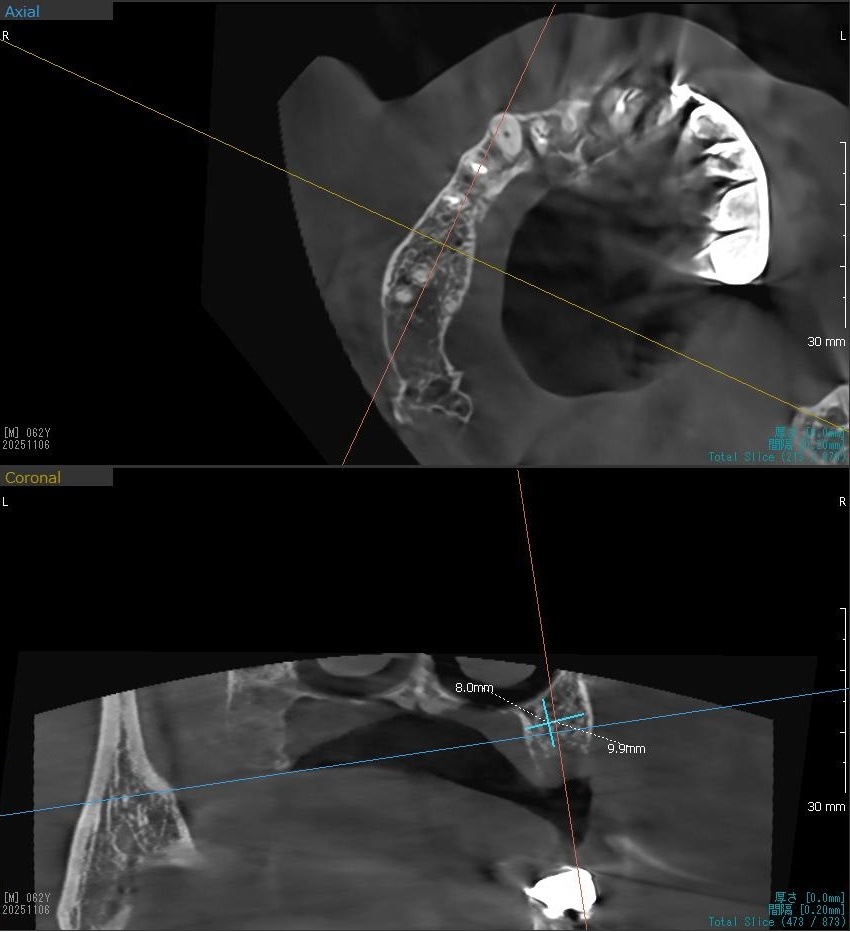

今回の患者様はインプラント植立を希望され、右上6番目の植立が決まりました。

ドリルの先端を細い物から徐々に大きい物に変えながら、植立するインプラント体のネジの部分を除いた胴の部分の太さに合わせた大きさの穴を開けていきます。

開けた穴に、専用道具を使ってネジを締めるように長さ2センチ程のインプラントを骨に埋め込んでいきます。